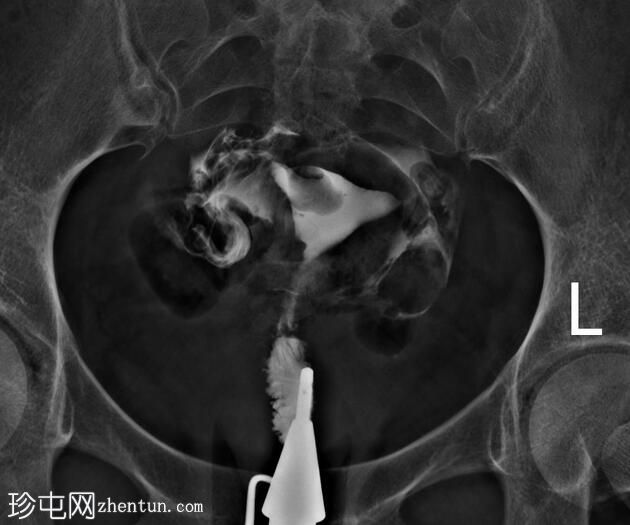

X线片

正位片

子宫内膜腔内可见一卵圆形充盈缺损,边缘光滑,强烈提示子宫内膜息肉的存在,生理盐水灌注子宫声学造影(未显示)证实了这一诊断。

鉴别诊断中还应考虑黏膜下肌瘤。